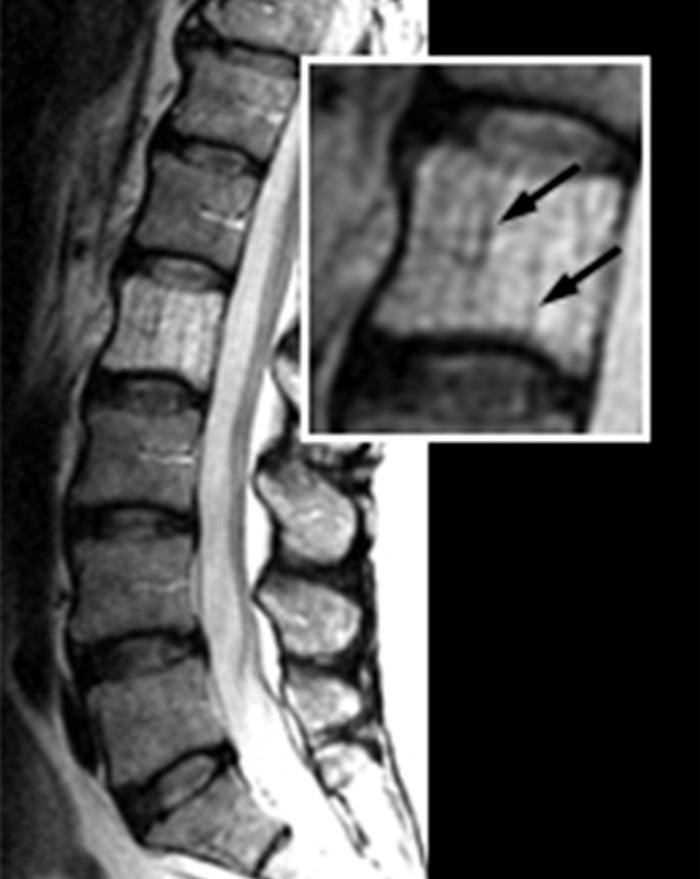

From www.researchgate.net

a. Sagittal MR imaging of the lumbar spine of a patient with hemangioma Spinal Hemangioma Cancer Although these tumors are most frequently benign and. Although these tumors are most frequently benign and. Spinal hemangiomas are common primary tumors of the vertebrae. Spinal tumors can form anywhere in and along your spinal column, which includes your vertebrae, spinal cord and the tissues surrounding. Spinal hemangiomas are common primary tumors of the vertebrae. Vertebral hemangiomas (vhs) are the. Spinal Hemangioma Cancer.